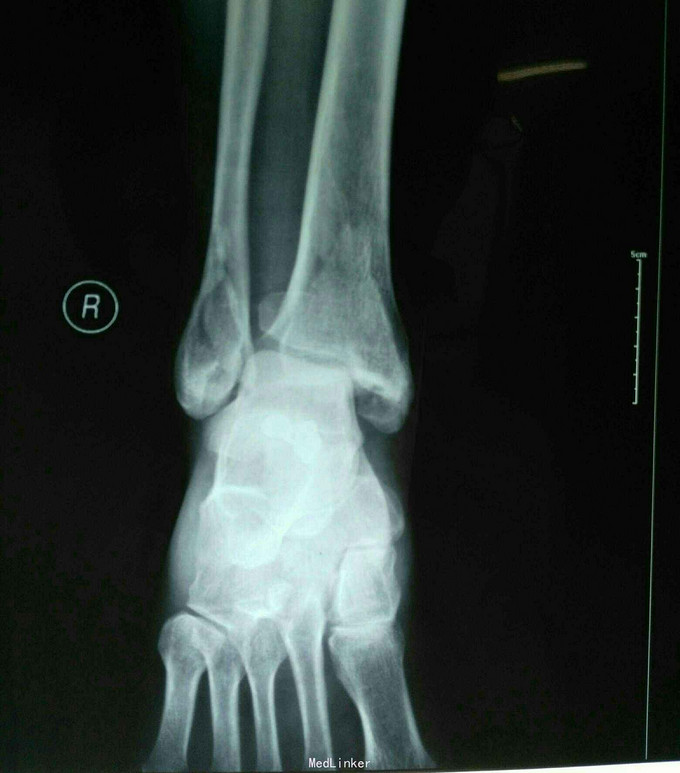

摔伤致右踝关节疼痛肿胀、活动受限3小时余 家属代述3小时前不慎摔伤致右踝关节,当即感疼痛,肿胀活动不利,未行任何治疗,急于我院就诊,经拍片查体后以右踝关节粉碎性骨折收入院。入院时,患者神志清,精神可,各项生命体征稳定,无恶心、呕吐,无头晕、头疼,纳食可,二便调。

专科检查:右踝关节压痛(+),肿胀,活动不利,可触及骨擦感,闻及骨擦音,皮下淤青,肢端感觉及血运可,足背动脉可轻微触及。 拍片示:右踝关节粉碎性骨折